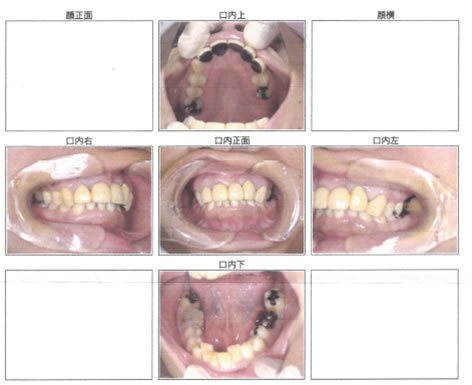

治療後

全ての歯がきれいにクリーニングされ、

歯ぐきの状態も改善しています。

治療前

歯周病菌は多くはありませんが一定数の菌数が見られます。

しっかりと治療を受けていただくことで、菌数がお幅に減少し、

殆どなくなり、状態が改善されています。

歯周ポケットが深い部分が多く、

出血も見られ、歯周病が進行していることがわかります。

歯周ポケットが浅くなり、歯周病の状態が改善されています。